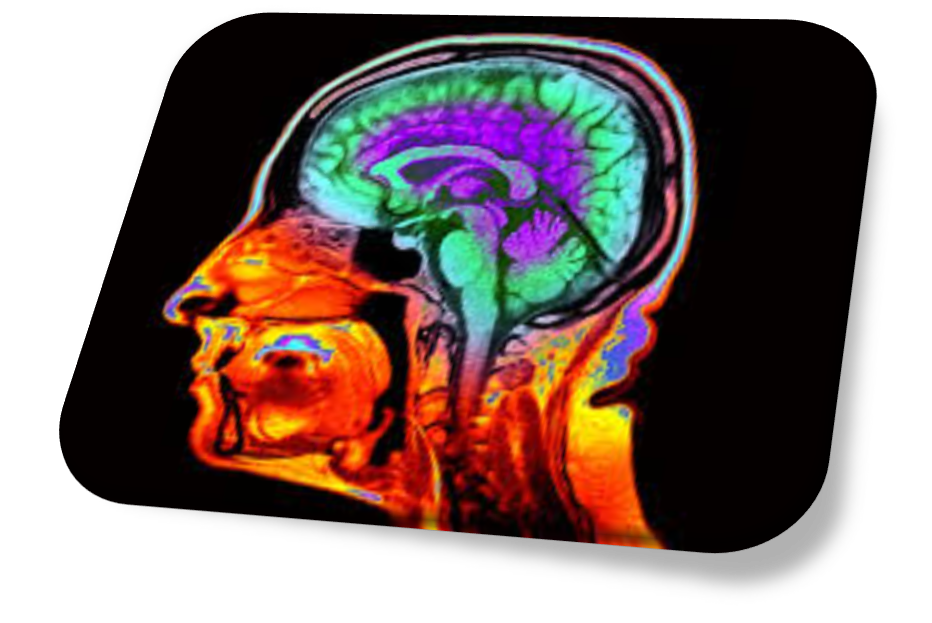

이에 비해, 듀크/오타고 연구에서 사용된 것은 이미 임상 현장에 널리 보급된 MRI다. 연구팀이 개발한 다니든PACNI는 알고리즘 기반 바이오마커로, 표준적인 뇌 MRI 이미지를 이용해 노화 속도를 추정한다.

“단 한 번의 뇌 스캔으로 노화 속도를 추정하고, 질병 위험을 예측할 수 있게 되었습니다.”라고 연구 논문의 제1저자이자 듀크 대학 임상심리학 박사 과정에 있는 이선 휘트먼은 말했다.

이 알고리즘은 5만 건 이상의 뇌 MRI 이미지와, 1972~1973년에 뉴질랜드에서 태어난 1037명의 피험자를 수십 년 동안 추적해온 유명한 다니든 연구의 데이터를 이용해 개발되었다.

듀크/오타고 연구의 노화 시계는 주요 구조적 지표(피질 얇아짐, 해마 위축 등)를 식별하여 뇌의 퇴화와 인지 기능 저하를 추정한다. 중요한 점은, 이 노화 시계가 세대 간 차이의 영향을 배제하고 순수하게 생물학적 노화만을 측정한다는 것이다.